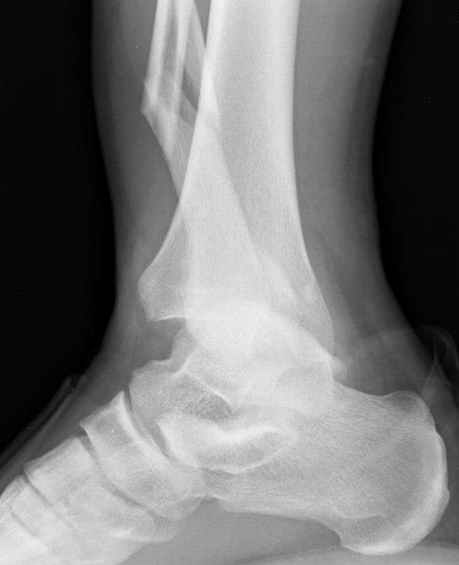

Неравномерность суставной щели может быть связана с разрывом глубокой порции дельтовидной связки и ротацией м/берцовой кости за счет поврежденных структур синдесмоза(репозиция ее на уровне перелома как-будто удовлетворительная).

По моему мнению,ассиметрия суставной щели обусловлена импрессией медиальной части суставной поверхности б/б кости. Да, позиционный винт здесь не лишен, но через 4 недели целесообразность его проведения сомнительна, брейс, ограничение осевой нагрузки достаточно.Есть еще деонтологические аспекты повторной операции, не все так плохо выполнено предыдущим доктором!

Импрессия медиальной части суставной поверхности бывает при супинационном механизме перелома лодыжек (тип А по классификации АО). Здесь механизм пронациия+наружная ротация (тип С, синдесмоз и межкостная мебрана повреждены),

перелом медиальной лодыжки отрывной, при этом в 20-30% бывает повреждение дельтовидной связки.

Клиновидность щели сустава следствие повреждения дельты, невосстановления длины малоберцовой или (хотел сказать "установки в гипсе", но оного, вроде,

нет)? Устранить бы причину. А равно как и тенденцию" к наружному подвывиху. Чрескостный остеосинтез - метод выбора.

Мое мнение, что никакой ротации малоберцовой кости здесь нет и синдесмоз тоже впорядке. Все дело в некачественно репозиции медиального мыщелка. Скорее всего его или немного ротировали при операции или сместили латерально. Более склонен ко второму варианту.

Конечно, компьютерный томограф более информативный метод, но с помощью недорогого обычного стандартного в нейтральном положении стопы: прямого, бокового и косой (ankle mortise) ренгенологического метода можно получить полную информацию о повреждении голеностопного сустава, а сравнительный снимок с другой стороны подтвердить наличие повреждения.

При реконструкции голеностопа, о важности восстановления длины малоберцовой для профилактики пост травматического артроза разбирали в предыдущих дискуссиях. Нарушенную биомеханику голеностопа без восстановления длины малоберцовой, не восстановить только швом медиальной связки.

Расширенная медиальная щель более чем на 4 мм и укорочение малоберцовой более чем 2 мм, а перелом заднего края большеберцовой смещения более 2мм с вовлечением 30% поверхности сустава, считается отходом от нормы голеностопного сустава, и подлежит к оперативному вмещательству.